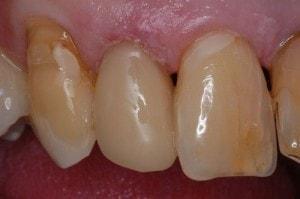

#7 completed

-

#’s 7 & 8 completed

Lingual view of completed restorations

Note how #7 is lingual #8. With the Greater Curve Matrix overlapped anterior teeth do not present a challenge.

Completed restorations